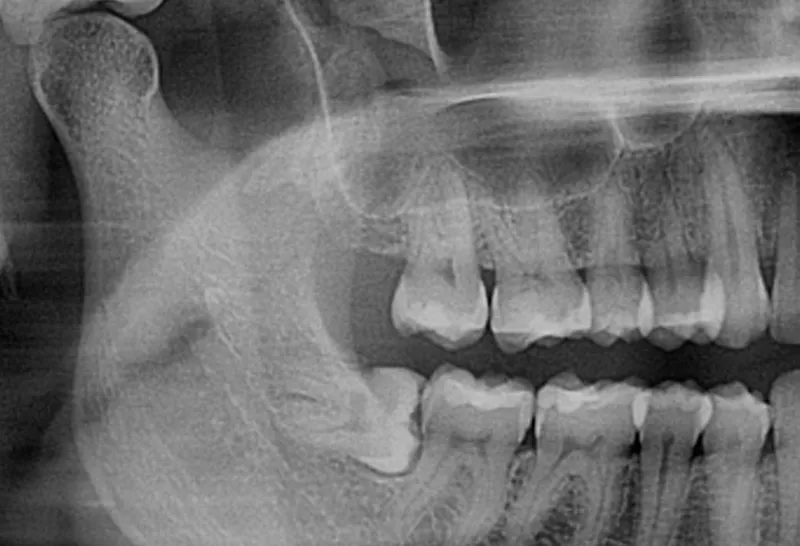

Análise de exames de imagem (ênfase em tomografia)

Exodontias simples e complexas (ênfase em terceiros molares)